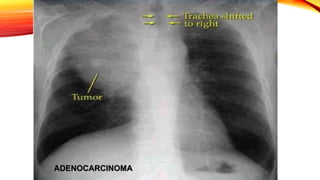

Carcinoma escamoso

• Masa central de gran tamaño que a menudo se cavita.

Carcinoma de célulaspequeñas • Localización prehiliar en el 80% y se asocia a adenopatías mediastinicas. Carcinoma escamoso • Masa central de gran tamaño que a menudo se cavita. Adenocarcinoma • Se presenta como nódulo o masa de distribución periférica y ocasional presencia de broncrograma aéreo. • Carcinoma bronquioalveolar presenta broncograma aéreo y puede presentar cavitación Farreras & Rozman Medicina Interna 17 edicion, capitulo 81, Pag 726.